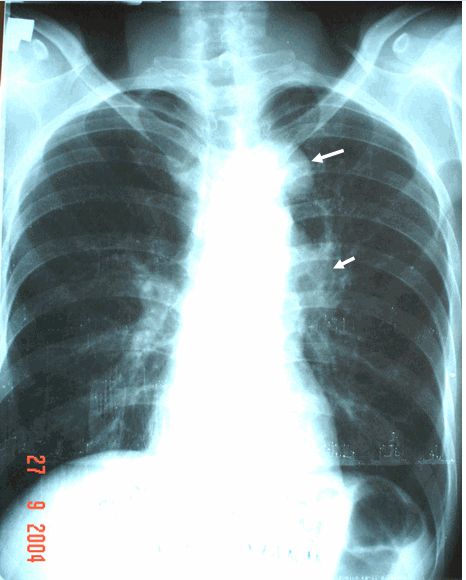

Hạch trung thất to và đối xứng trong Sarcoidose

Hạch trung thất to và đối xứng trong Sarcoidose trên phim chụp x quang ngực. Mời các bạn tham khảo một số thông tin dưới đây để hiểu rõ hơn nhé!